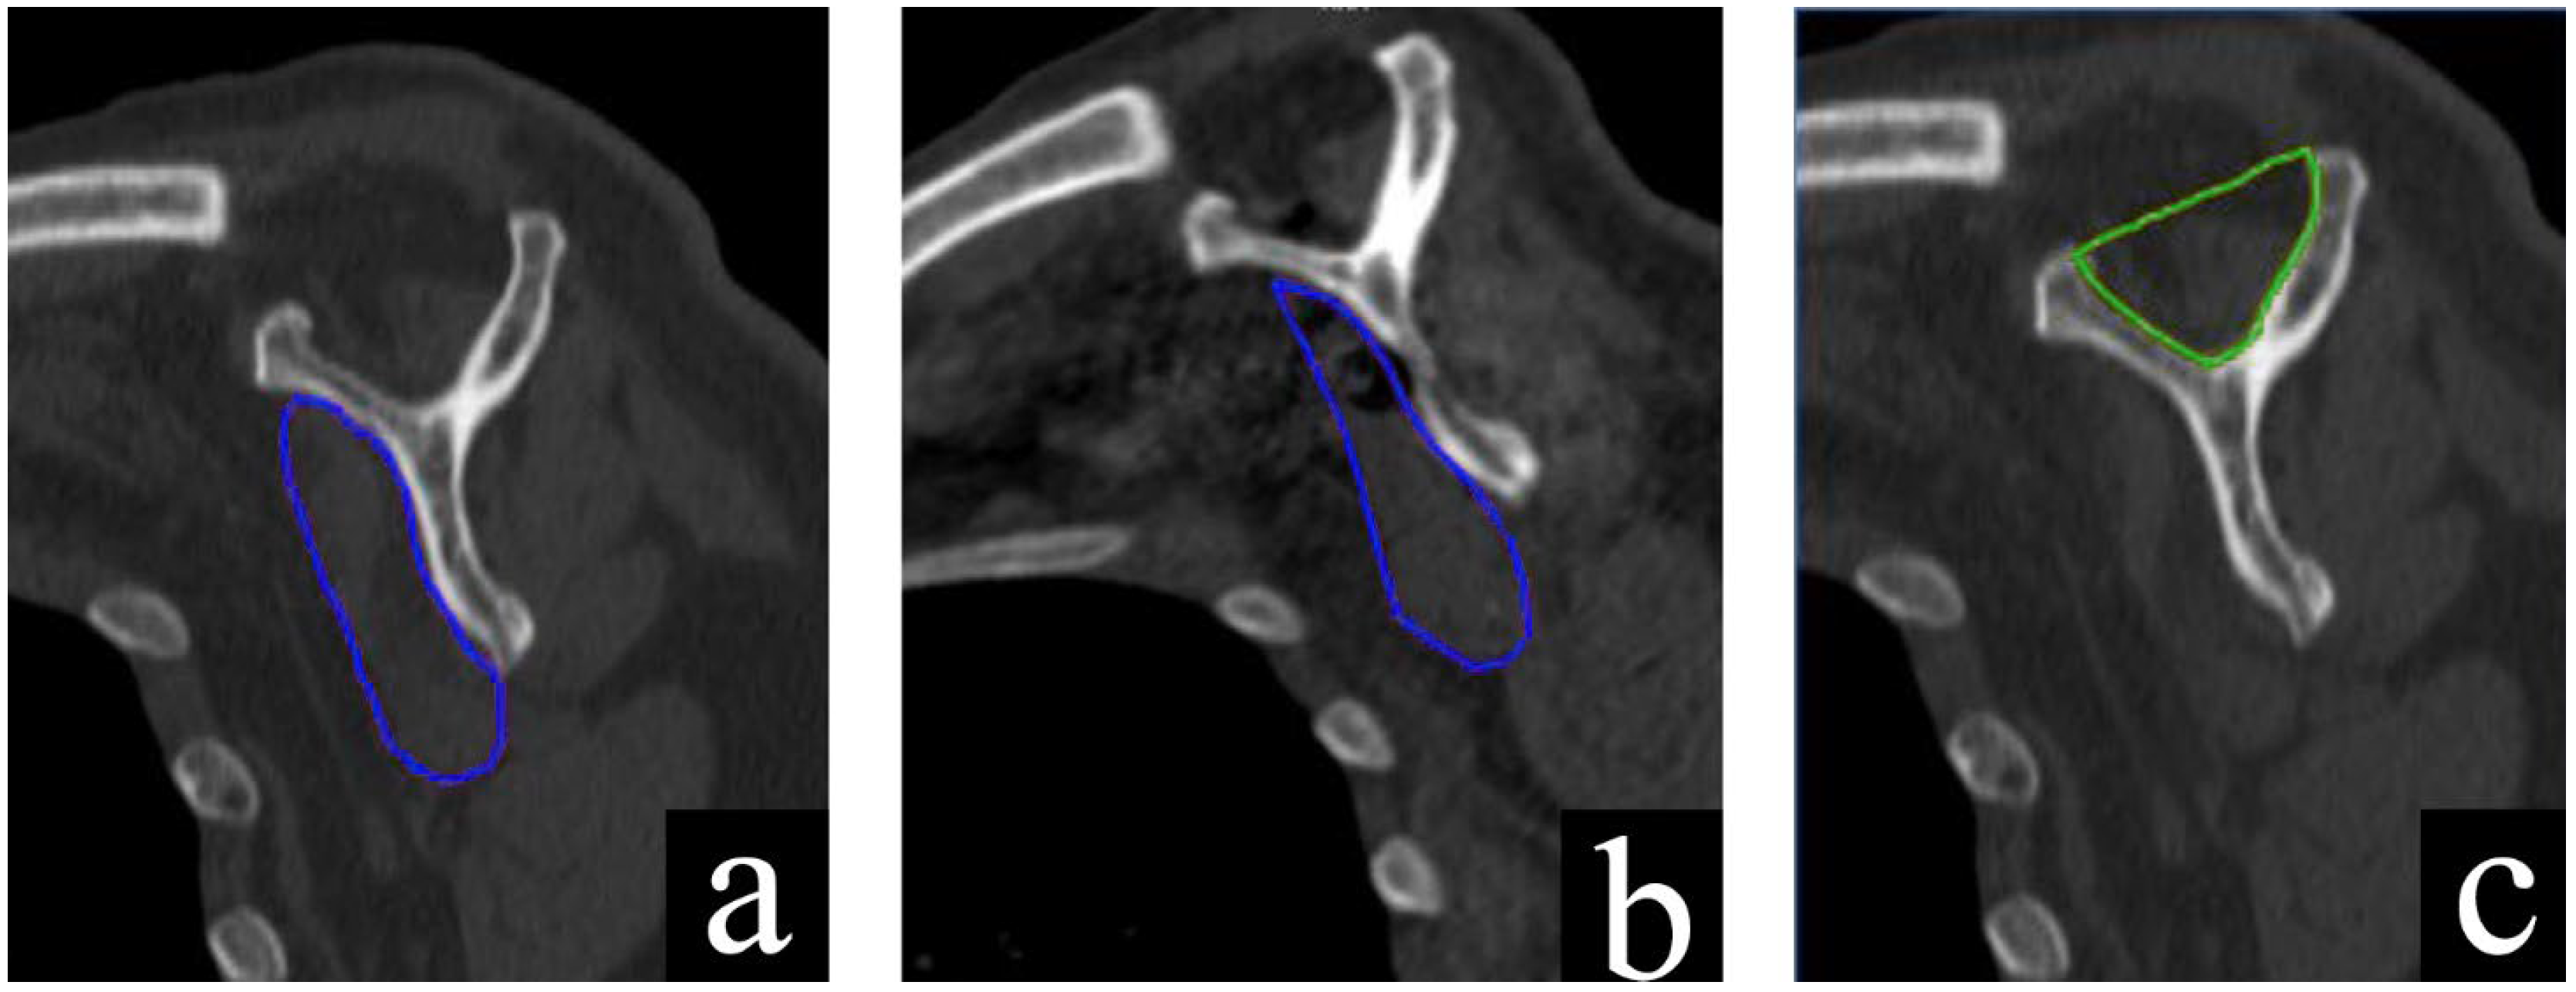

2.4. CT Evaluation

| SMCSA | Subscapularis muscle cross-sectional area |

| SFCSA | Supraspinatus fossa cross-sectional area |

- De Carli, A.; Gaj, E.; Drogo, P.; Viglietta, E.; Polidori, T.; Forlenza, E.; Patel, B.H.; Ferretti, A. Computer Tomography Assessment of the Subscapularis after Reverse Shoulder Arthroplasty and Subscapularis Repair: Reduction in Subscapularis Size Do Not Affect Clinical Outcomes. Semin. Arthroplast. JSES 2021, 31, 131–138. [Google Scholar] [CrossRef]

- Terrier, A.; Ston, J.; Dewarrat, A.; Becce, F.; Farron, A. A Semi-Automated Quantitative CT Method for Measuring Rotator Cuff Muscle Degeneration in Shoulders with Primary Osteoarthritis. Orthop. Traumatol. Surg. Res. 2017, 103, 151–157. [Google Scholar] [CrossRef]

- Thomazeau, H.; Rolland, Y.; Lucas, C.; Duval, J.-M.; Langlais, F. Atrophy of the Supraspinatus Belly Assessment by MRI in 55 Patients with Rotator Cuff Pathology. Acta Orthop. Scand. 1996, 67, 264–268. [Google Scholar] [CrossRef]